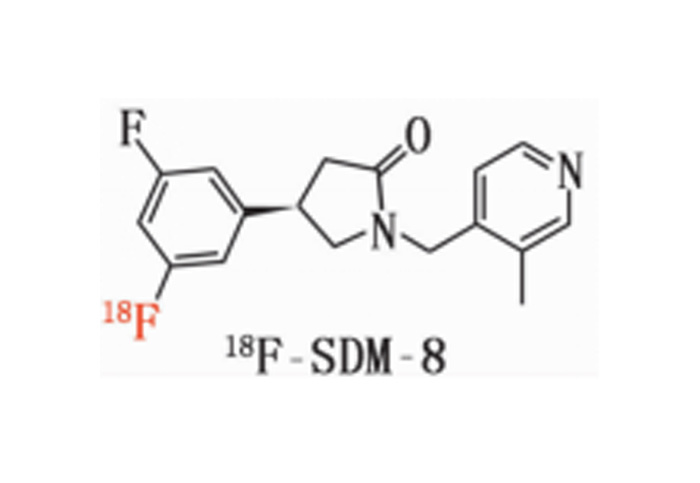

對(duì)18F、11C、68Ga、等核素示蹤劑的(de)合成與國(guó)外(wài)主流示蹤劑合成平台達到(dào)同一(yī)水(shuǐ)<平;